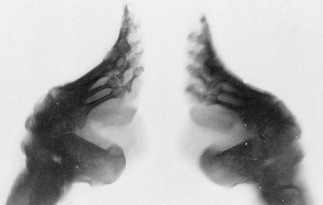

Foot binding was the process of breaking and binding women's feet, starting when they were young girls and continuing throughout their lives. The practice dates to the 10th century and carried on for over a thousand years. All toes except the largest were broken, folded under the sole of the foot and tightly bound with cotton or silk bandages. The feet were cleaned every few days and the wrapping tied increasingly tighter each time.

Foot binding prevented little girls from having a normal, playful childhood. They had difficulty moving around due to the pain of having their feet bound. In pain, rendered unusable, the body permanently trying to heal wounds that would be repeatedly inflicted upon it again and again. Unable to walk without pain, run or do sports, these young girls grew into women with jobs that allowed them to use their hands and sit all day.